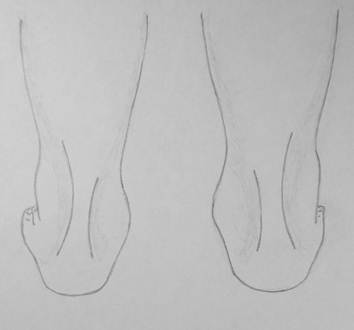

Вальгусные и варусные пятки

Пятки

стоящего человека занимают определенное положение: или абсолютно ровное по

осевой линии голеней, или слегка расставленое в стороны. Расставленные в

стороны пятки в виде сзади называются вальгусными пятками и это нормальное

явление. Очень часто его ошибочно называют вальгусными стопами, что

неправильно. При ряде заболеваний пятки могут принимать установку с отклонением

их кнутри, что называется варусными пятками. Варусные пятки являются

патологическим явлением.

Слева

изображены вальгусные пятки у ребенка 3 лет, что является совершенно нормальным

явлением. Справа – варусные пятки у ребенка 15 лет с синдромом Шарко – Мари –

Тута, который проявляется нарушением проведения нервных импульсов к мышцам и их

атрофией.